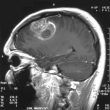

Rezultate uimitoare la testele pe oameni: Virusul herpesului oral, modificat în laborator, a distrus tumorile canceroase23-09-20224.785Sănătate

`Înfometarea celulelor` este o nouă metodă revoluționară în lupta cu tumorile - Descoperirea făcută de cercetătorii israelieni12-09-20224.339Știrile Zilei

Un medic de la Institutul Oncologic Bucureşti atrage atenția: Leacurile 'din auzite' înrăutățesc starea de sănătate a pacienților cu cancer09-07-202211.233Social